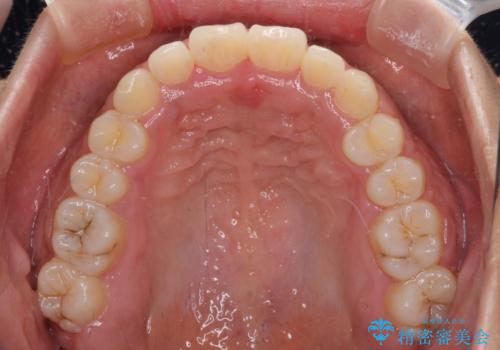

- 上下前歯の叢生を気にして来院された患者様です。

当初はインビザラインにて治療を開始しましたが、自己管理による治療が難しくなり、ワイヤー矯正へ転換して継続しました。

2年ほどインビザライン矯正を続けましたが、終了することができず、ワイヤーへ転換後は1年弱で終えることができました。